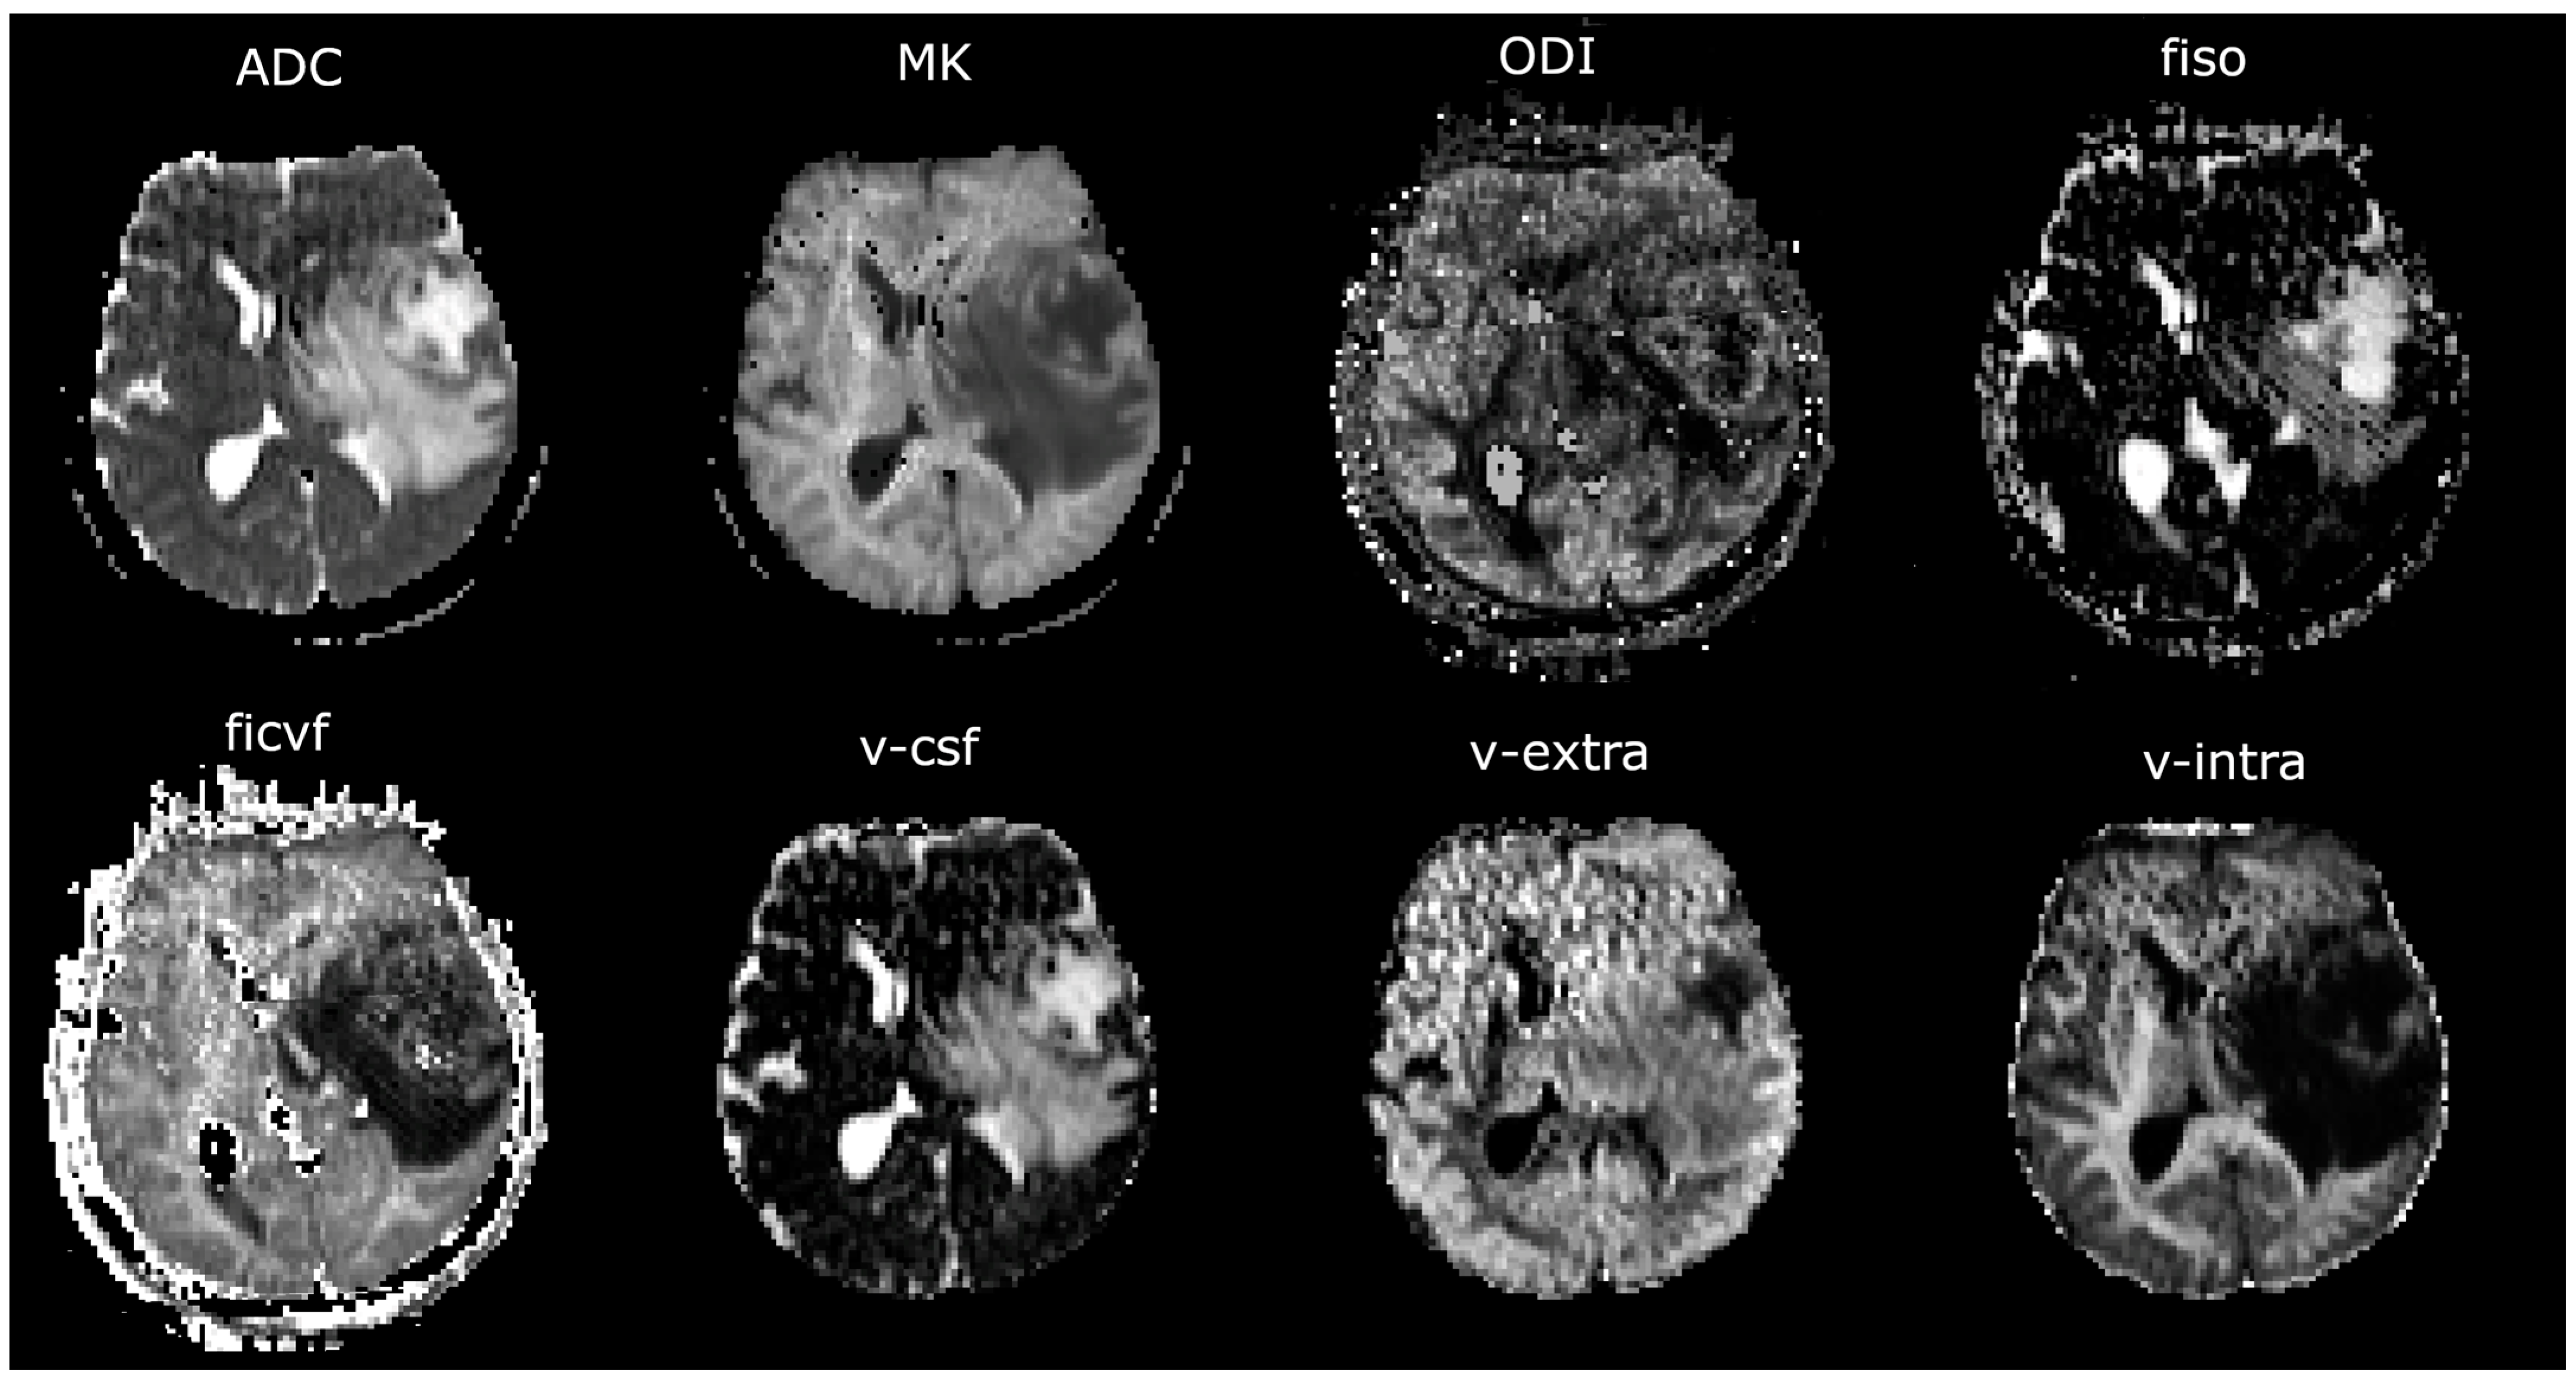

2.4. Image Analysis